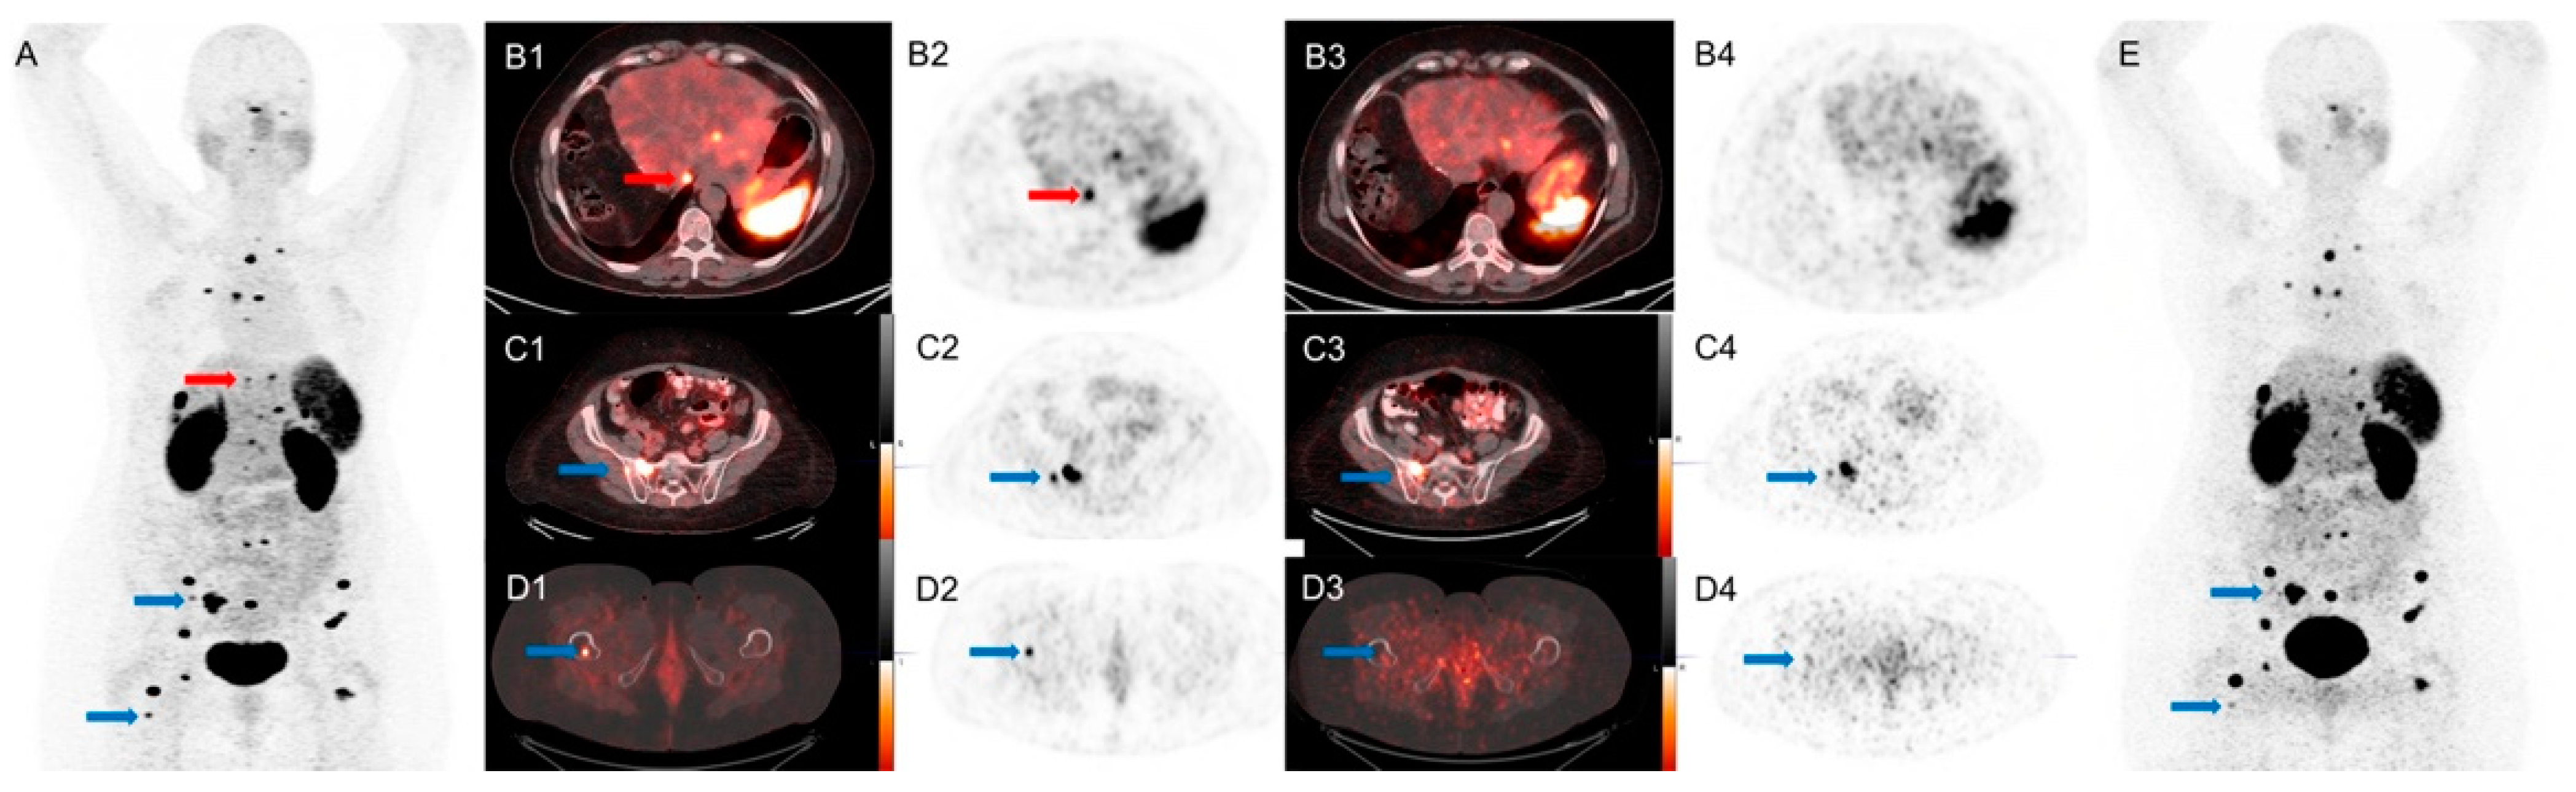

3.2. Results When SiPM PET/CT Was Used First Followed by Conventional PET/CT

3.3. Results When Conventional PET/CT Was Used First Followed by SiPM

4. Discussion